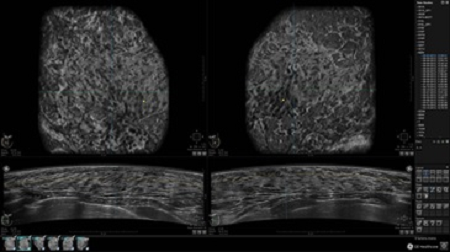

• Многооконный просмотр: 4 - 12 изображений

• Стандартизованная ориентация изображения: «толстый срез» в коронарной плоскости; поперечная; сагиттальная плоскость; радиальный и антирадиальный поворот изображения; просмотр исключительно области интереса

• Изменяемая толщина среза: 0,5 - 10,0 мм (шаг 0,5 мм)

• Срез: 0,5 - 2,0 мм (шаг 0,5 мм)

• Одновременный просмотр двух изображений для сопоставления в коронарной плоскости